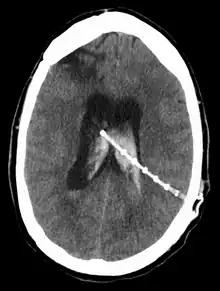

Une dérivation du liquide cérébrospinal (ou shunt cérébral) est un dispositif implanté de façon permanente à l’intérieur de la tête et du corps pour évacuer l’excès de liquide du cerveau. Elle est couramment utilisée pour traiter l'hydrocéphalie, le gonflement du cerveau dû à une accumulation excessive de liquide céphalo-rachidien (LCR). Si rien n'est fait, l'excès de LCR peut entraîner une augmentation de la pression intracrânienne (PIC), ce qui peut provoquer un hématome intracrânien, un œdème cérébral, un écrasement du tissu cérébral ou une hernie[1]. Le drainage assuré par une dérivation peut atténuer ou prévenir ces problèmes chez les patients souffrant d'hydrocéphalie ou de maladies associées.

Les dérivations se présentent sous diverses formes, mais la plupart d'entre elles sont constituées d'un boîtier de valve relié à un cathéter dont l'extrémité inférieure est généralement placée dans la cavité péritonéale. Les principales différences entre les dérivations résident généralement dans les matériaux utilisés pour les construire, les types de vannes utilisées et le fait que la vanne soit programmable ou non[2].

L'emplacement de la dérivation est déterminé par le neurochirurgien en fonction du type et de l'emplacement du blocage provoquant l'hydrocéphalie. Tous les ventricules cérébraux sont candidats à la dérivation. Le cathéter est le plus souvent placé dans l'abdomen, mais d'autres emplacements incluent le cœur et les poumons. les dérivations peuvent souvent porter le nom de la voie utilisée par le neurochirurgien. L'extrémité distale du cathéter peut être située dans à peu près n'importe quel tissu comportant suffisamment de cellules épithéliales pour absorber le LCR entrant. Ci-dessous quelques plans de routage courants pour les dérivations cérébrales :